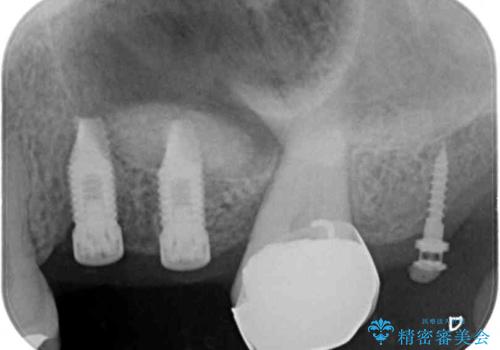

ブリッジの支台を抜歯したことで2本のインプラントが必要であり、その後方はインプラント埋入に必要な骨量が不足していたため、上顎洞粘膜の挙上を行うこととしました。

また、残っている最後方歯は手前に倒れてきていたため、部分矯正により奥に移動させてから、インプラント埋入を行うこととしました。

部分矯正期間中はアンカースクリューやフック、ゴムなどが粘膜にあたり、大変な思いをすることになりましたが、そのおかげでインプラント補綴した歯と最後方歯の位置が非常に良好となり、まるでご自身の歯のように咬むことができるようになりました。